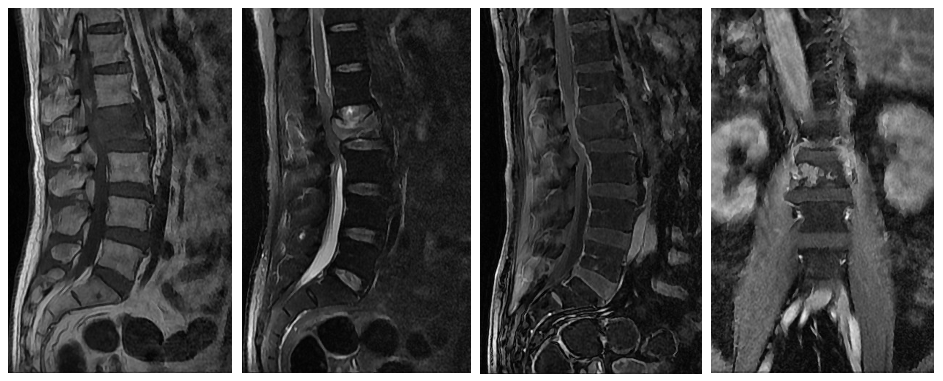

● 男性,69岁

● 病史:患者于2021年9月初无明显诱因感左侧背痛,疼痛为刀割样,夜间痛尤甚,白天疼痛缓解,无明确姿势性缓解,患者理疗疼痛无明显缓解,14天前患者突然感腰部疼痛,疼痛性质同颈部疼痛,10月26号于华东医院疼痛科就诊行MR检查示腰2椎体内病灶伴病理性骨折,向后突入椎管,椎管狭窄,马尾受压,10月27号患者下肢不能行走,伴痉挛性疼痛。

● 目的:患者拟行腰2椎体肿瘤切除术,术前行腰动脉栓塞术减少术中出血。

临床资料

桡动脉鞘怎么读R.A.V.I.Club微课堂 · 经桡动脉外周介入之长征篇第八期_https://www.jmylbn.com_新闻资讯_第6张